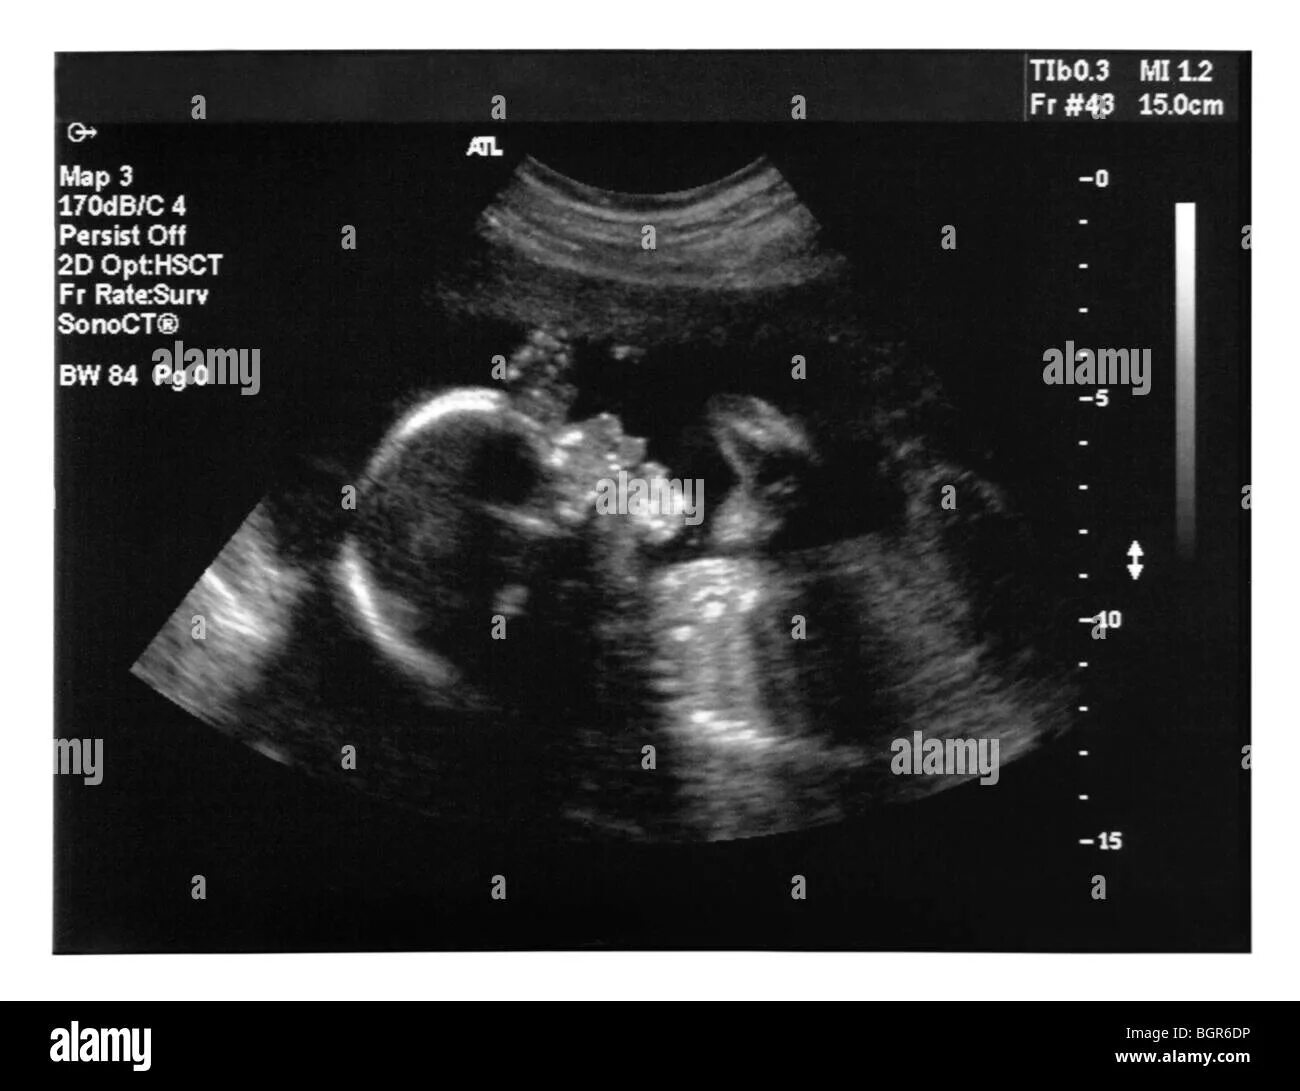

18 недель как выглядит малыш